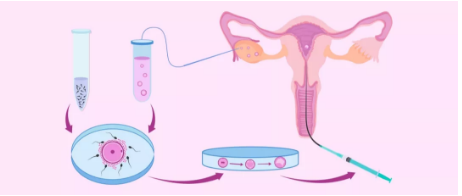

试管婴儿是

分别从男人和女人体内取出发育成熟的精子和卵子

在体外模拟的受精环境下

结合成受精卵

筛选出质量较高的受精卵

植回到子宫中

当受精卵在子宫壁上成功着床

试管婴儿就做成功了